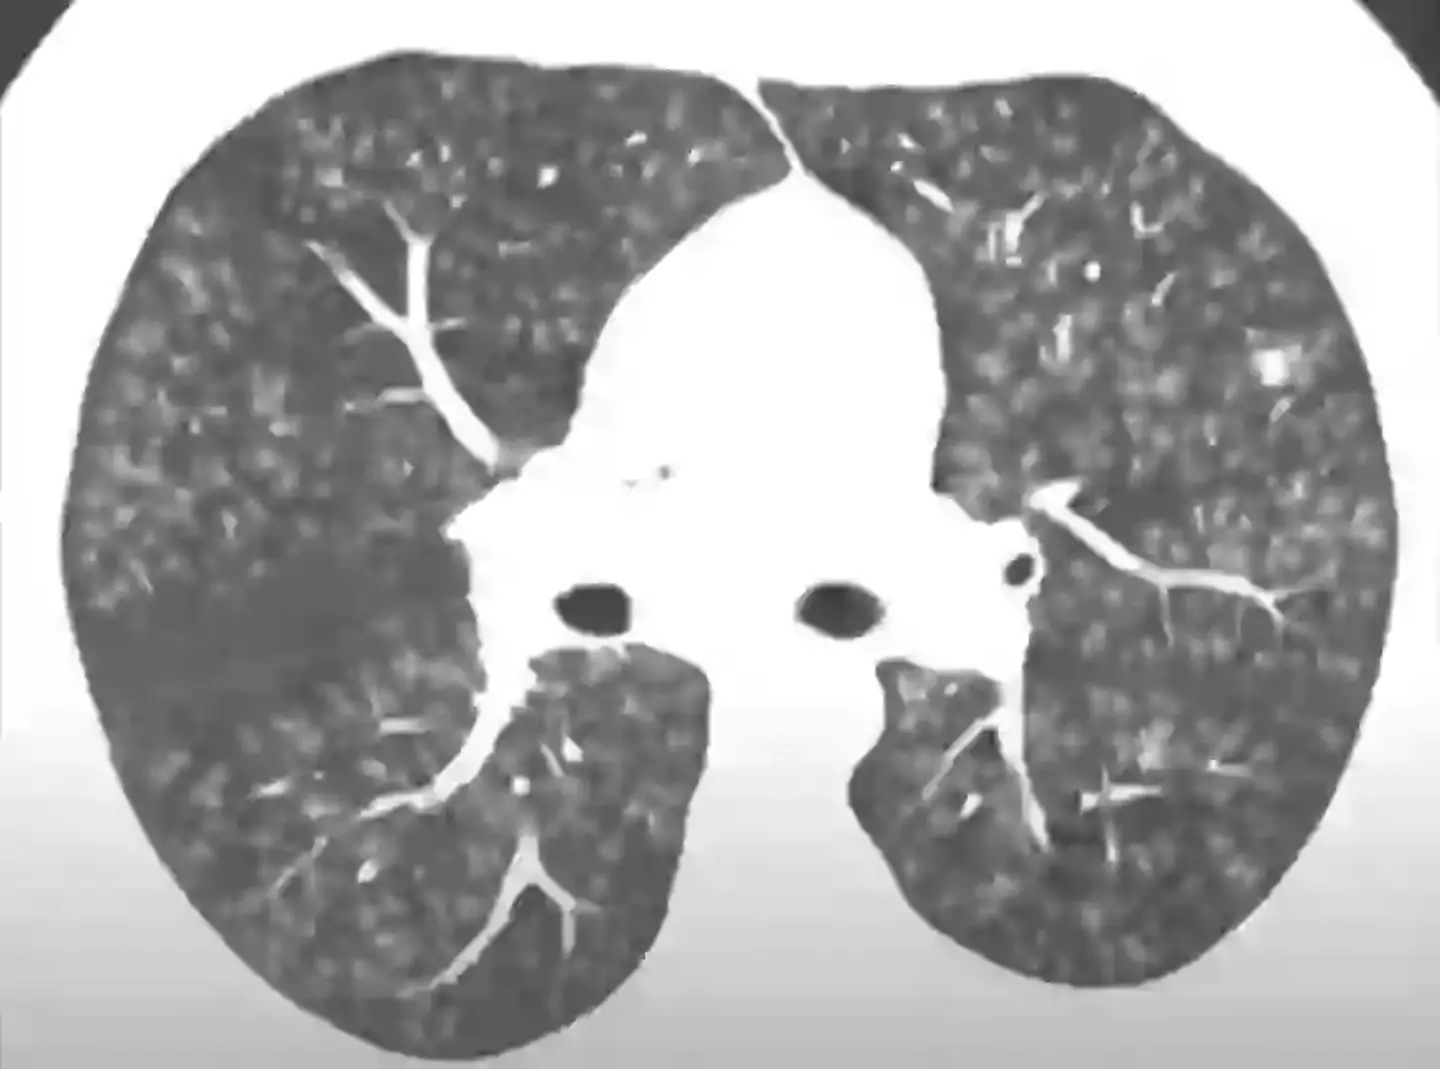

In a YouTube Short, a healthy pair of lungs are slapped beside a pair potentially suffering from diacetyl overexposure.

As you can see, the left-sided image - most likely a CT scan as chest X-rays are unreliable when diagnosing popcorn lung - depicts a speckled mess across the body's natural breathing apparatus, almost like a rash.